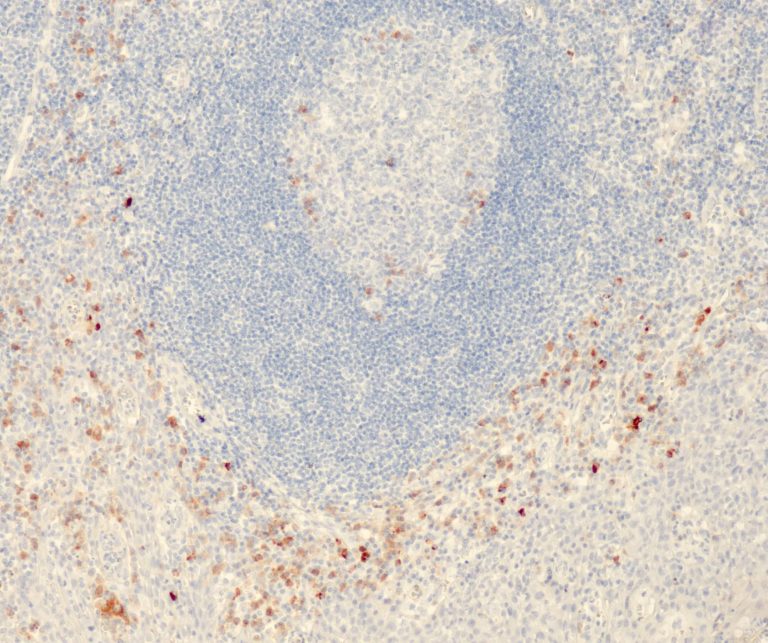

Vascular Pathology

Gastrointestinal (GI) Pathology

General Marker

Breast Pathology

Endocrine Pathology

Gynecological Pathology

Neuropathology

Infection Markers

Lung Pathology

Urinary Tract Pathology

Transplantation Pathology

Soft Tissue Pathology

Hematopathology